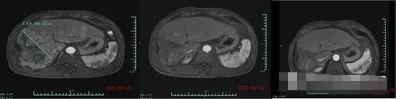

11 名晚期肝癌患者参与,其中9名可评估的受试者里,客观缓解率可达44.4%,疾病控制率达到77.8%。值得一提的是,有两名患者比较幸运,其中1位患者在治疗1个月后,肿瘤缩小80%以上。另1位在28天后靶向病灶肿瘤的直径由原来的133毫米,缩小到9毫米,并在3个月后核磁扫描,肿瘤几乎消退。